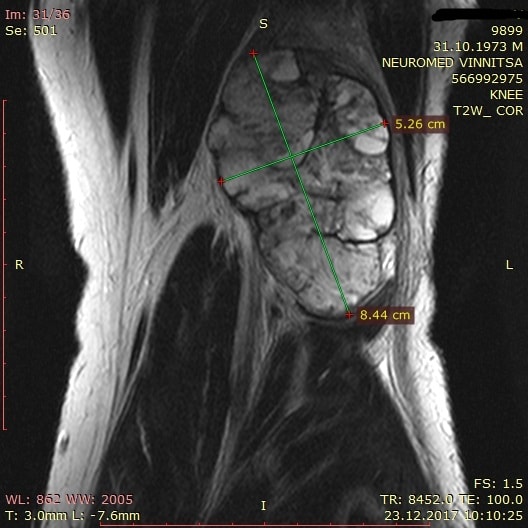

[Ortho] Новообразование на задней поверхности коленного сустава

Имя     : 200001-min.jpg